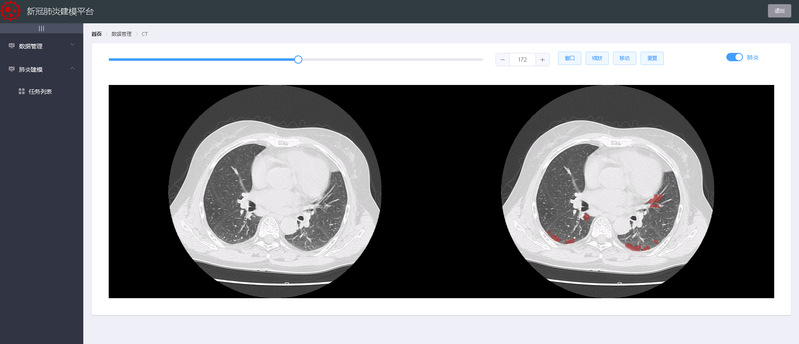

CT图像与肺炎区域对照